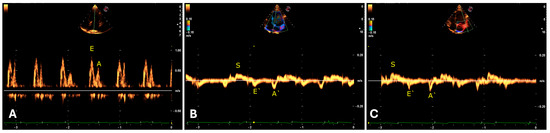

The jaguars remained under anesthesia for an average of 69.3 ± 7.5 min, including the time from dart administration to the administration of the reversal agent. The induction time after dart administration was 17.1 ± 4.3 min. The execution of the echocardiogram in the right (25.8 ± 4.7 min) and left (26.4 ± 2.8 min) parasternal windows totaled 52.2 ± 7.5 min. The average heart rate was 72 ± 18 beats per minute, with a sinus rhythm in ten animals and sinus arrhythmia in five jaguars (Figure 2).

Regarding the morphology of the QRS complex, an R and Rs pattern was observed in leads II, III, and aVF, with peak amplitude in lead II (Table 3) and a duration of 54 ms. In precordial leads, the QRS complex exhibited an rS morphology in V1 and r from V2 to V6 (Table 2), with an average electrical axis of 82 ± 13 degrees (Table 1) and variation from 20 to 110 degrees in the specimens studied (Figure 3).

Figure 2. Appearance of the P-QRS-T complex in limb and precordial leads in two jaguar specimens anesthetized with medetomidine and ketamine. (A): Male, 61.3 kg, 4 years old. Twelve leads (I, II, III, aVR, aVL, aVF, V1, V2, V3, V4, V5, and V6), speed 50 mm/s, sensitivity 10 mm/mV. Sinus rhythm with a heart rate of 66 beats per minute. (B): Female, 44.6 kg, 8 years old. Twelve leads (I, II, III, aVR, aVL, aVF, V1, V2, V3, V4, V5, and V6), speed 50 mm/s, sensitivity n. Sinus arrhythmia with a heart rate ranging from 44 to 71 beats per minute.